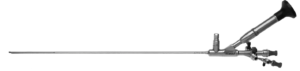

Reteroscopio semirígido

- Marca R. Wolf

- Lente de 5 °

- 2 Canales de 6.5/8.5 FR

Reteroscopio semirígido

- Marca R. Wolf

- Lente de 5 °

- 2 Canales de 6.5/8.5 FR